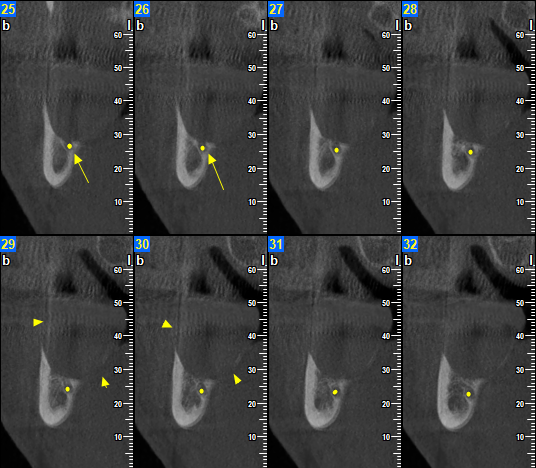

Τον Φεβρουάριο του 2024 ο ασθενής παραπέμφθηκε για CBCT άνω και κάτω γνάθου προκειμένου να προχωρήσει σε οδοντιατρικές εργασίες. Στο CBCT παρατηρήθηκε η παρουσία μικρού μεγέθους υπόπυκνης αλλοίωσης στο πρόσθιο χείλος του δεξιού κλάδου της κάτω γνάθου η οποία είχε προκαλέσει λύση των συμπαγών πετάλων.

Όπως αποδείχθηκε επρόκειτο για Αδαμαντινοβλάστωμα, και συνεπώς υποτροπή της αρχικής βλάβης που πρωτοεμφανίστηκε προ 3ετίας!